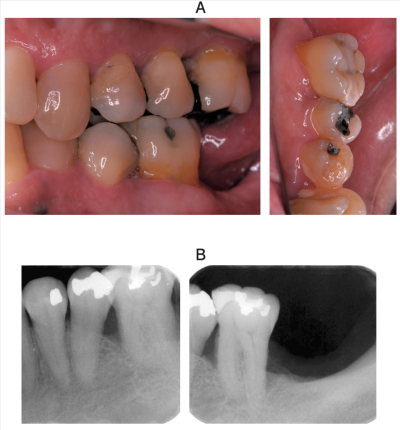

52歳の女性。左側の下顎臼歯部の歯肉腫脹を主訴として来院した。⎾6 に根分岐部病変は認めない。慢性歯周炎と診断し歯周基本治療を行った。初診時の口腔内写真とエックス線写真を別に示す。